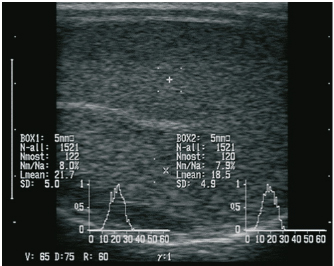

The andrological examination included the documentation of testicular parameters such as length, width, thickness (height) (using a testimeter according to Podany), and testicular consistency (by manual palpation performed by an experienced veterinarian), which was classified into five levels (level 1=soft elastic to level 5=coarse). Sonographic examination of the testes was performed using a Honda HS-1500VET ultrasound scanner (Honda Electronics Co., Ltd., Tokyo, Japan). A 50-mm multifrequency transrectal ultrasound probe (HLV-375M; 7.5 MHz) was used, following previous studies by Pugh et al. (1990) and Gouletsou et al. (2003). For better coupling of the ultrasound probe, the scrotum was sheared and shaved. Five images were obtained per testicular side (1× longitudinal section, 2× transverse section, 1× epididymal head, and 1× epididymal tail). In the longitudinal section and the two cross-sections, the region of interest (ROIs) for gray scale analysis [gray scale normal distribution, mean of gray scale distribution (Lmean), standard deviation, modal value for the most frequently found gray pixels (Nmost), and maximum value (N-all)] were analyzed. Two ROIs, each 0.25 cm² in size, were defined per image, each located between the skin line and on either side of the rete testis according to the protocol of Kauffold et al. (2011) (Fig. 1).

Fig. 1. Sonographic image of the testicular tissue (Honda HS- 1500 VET, 7.5 MHz, transrectal probe) presenting moderate echogenicity, and the mediastinum testis presenting as a hyperechogenic structure. The ROIs were located on both sides of the mediastinum testis with a basal area of 0.25 cm2.

In the sonographic examinations, the testicular tissue was found to be homogeneous with medium echogenicity in all cases. The mediastinum testis was hyperechogenic (Fig. 1), while the epididymal tissue was clearly hypoechogenic and heterogeneous. The results of the gray scale analysis, presented in Table 2, did not show a significant effect of treatment (p > 0.05).

Table 2. Results of quantitative gray scale analysis by sonography (Honda HS-1500 VET, 7.5 MHz, transrectal probe) with the corresponding arithmetic mean of Nmost (modal value for the most frequently found gray pixels) and Lmean (mean of gray scale distribution) values of rams from treated group (1) and control group (2).